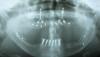

Беззубый УжОс Опубликовано 22 апреля, 2010 Поделиться Опубликовано 22 апреля, 2010 (изменено) Добрый день, уважаемые спецы!Моя старая тема http://forum.stom.ru/index.php?showtopic=5646&st=0.. За последние время определилась с тем, что надо сделать и привожу план в исполнение.Удалены оставшиеся корни на ВЧ.Сделана остеотомия обеих челюстей, чтобы исправить прикус. Подсажена собственная кость.Свежий снимок( через 2 недели после операции) выкладываю. У меня по нему возникли вопросы . Помогите плз1.После остеотомии все какое-то перекошенное 2. На НЧ слева( на снимке) почему то кости значительно меньше. Добиться от оперировавшего доктора не подсаживал там, или мало , или вообще рассосалась не удается. Говорит, что результатом доволен.3. Оставшиеся зубы сильно наклонились . Можно ли их в таком виде накрывать коронками? И когда. Хирург сказал, что хоть сейчас. После операции прошел месяц. И вопросы по дальнейшим действиям. Через 4-6 мес, если приживется нормально кость, ставить импланты.НЧ-по 2 с каждой стороны и на них по 3(4????) зубаВЧ.........10 (8?????????) и на них 12 ( 14?????) зубов???????? Процесс, мягко говоря, очень затратный Поэтому интересует наименее дорогой ( без ущерба надежности и качеству) вариант. Изменено 22 апреля, 2010 пользователем Беззубый УжОс Ссылка на комментарий

Беззубый УжОс Опубликовано 6 июля, 2010 Автор Поделиться Опубликовано 6 июля, 2010 (изменено) Уважаемые доктора, подскажите плз-нормально ли идет процесс приживления подсаженных костных блоков?http://s14.radikal.ru/i187/1007/b8/422b84ca9c83t.jpgэто картина через 3 мес после операции А то почитала http://forum.stom.ru/index.php?showtopic=11273 и страшновато........вдруг тоже.......... Изменено 6 июля, 2010 пользователем Беззубый УжОс Ссылка на комментарий